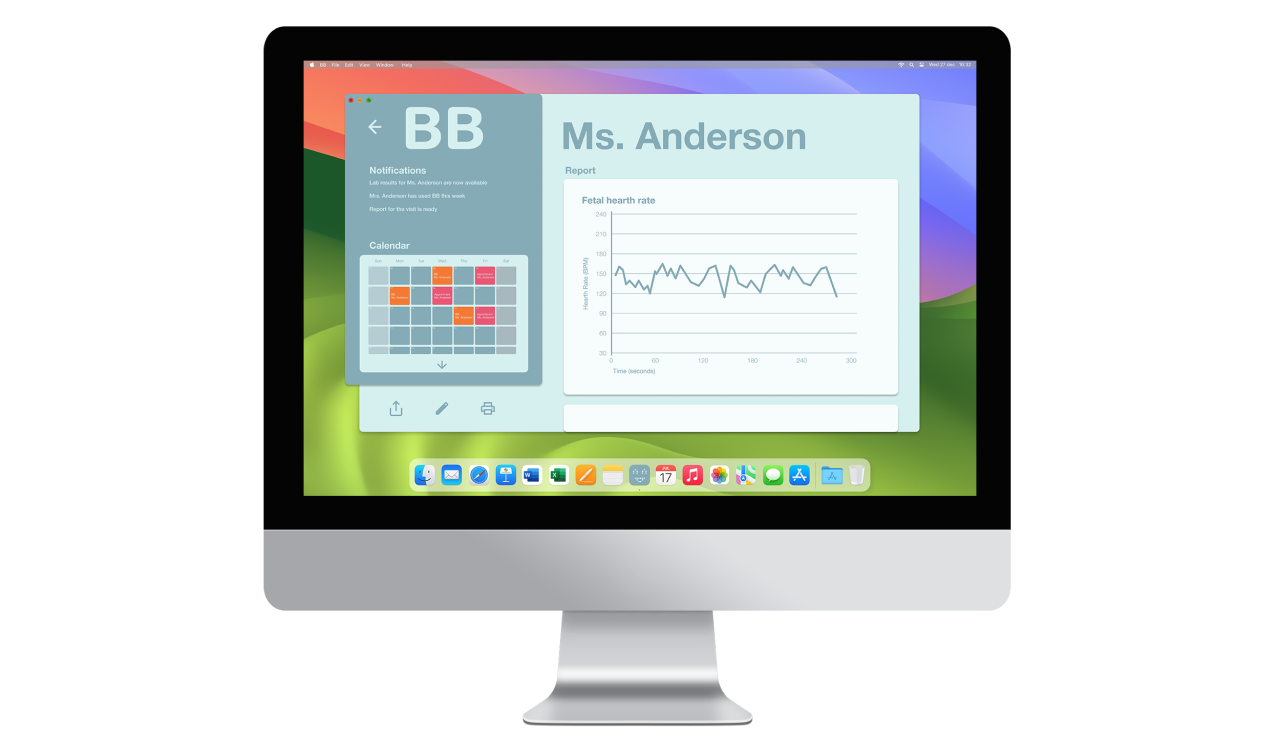

(2) B-B [product-service system for pregnancy monitoring]

B-B is a product-service system that connects pregnant women with their gynecologists through a monitoring device that tracks key health parameters while strengthening the emotional bond with the unborn child. It fosters closer relationships and more holistic, emotionally connected prenatal care.

The system includes a handheld domestic device that non-invasively monitors key biometric data with sensors like doppler ultrasound and PPG. Integrated into existing healthcare frameworks, it sends clinical reports and alerts providers when issues are detected.

The gynecologist’s user experience prioritizes minimal invasiveness and comfort, incorporating alert notifications for irregularities during monitoring. Additionally, a desktop interface allows access to data reports and appointments, benefiting both gynecologists and administrative staff. Administrative access enables efficient scheduling of device activations, enhancing coordination within the healthcare system.